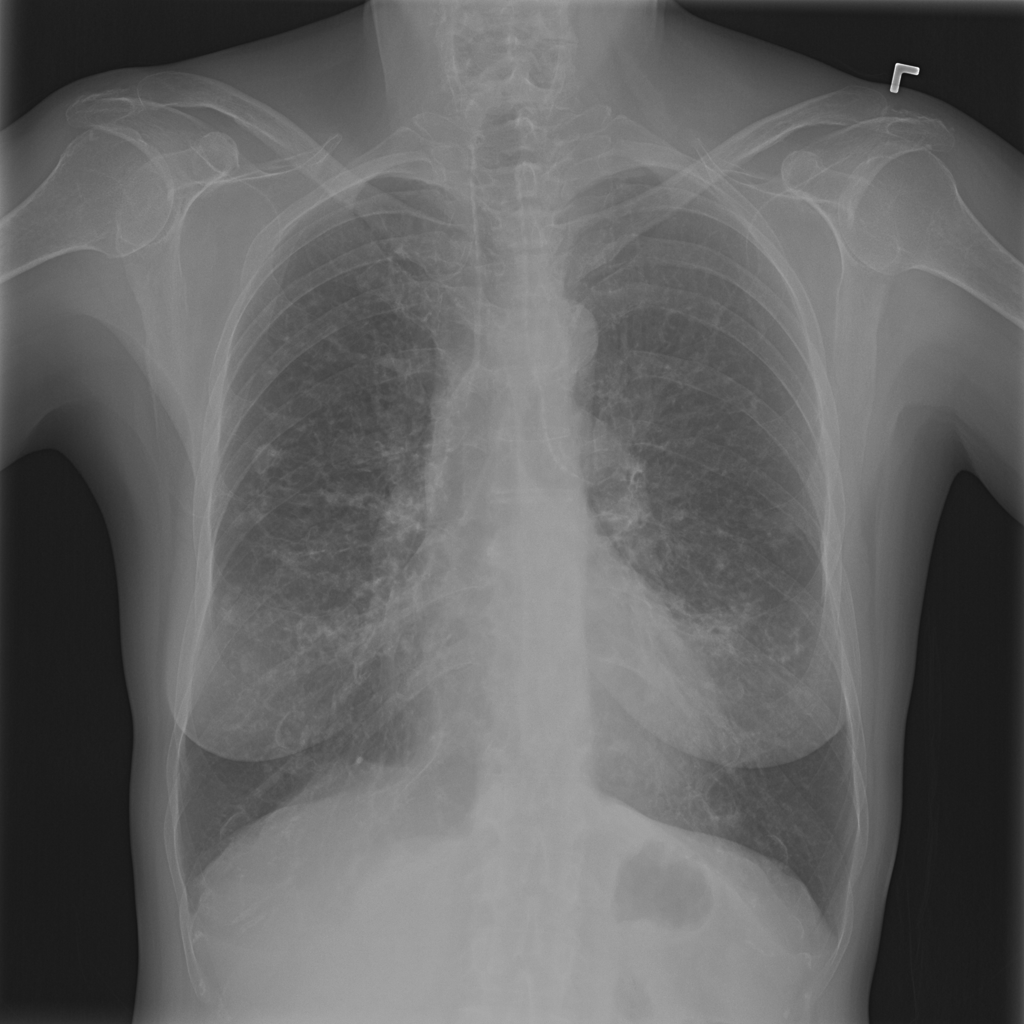

PAT-531A · IMG-006Consolidation

PAT-531A · IMG-006

PA